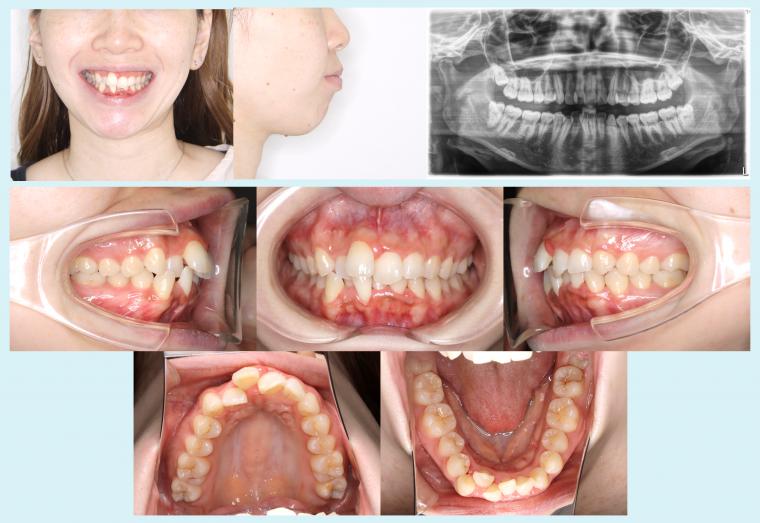

2026.03.31 #51 矯正用インプラントアンカーを用いてオートローテーションを図った症例 歯ならび、出っ歯が気になるとのことで来院された患者様です。治療前は、上下とも歯並びがデコボコして、横顔は口元がやや突出している様子でした。レントゲンの分析では、上下とも前歯が唇側に傾斜している状態でし... 症例集(表側矯正)